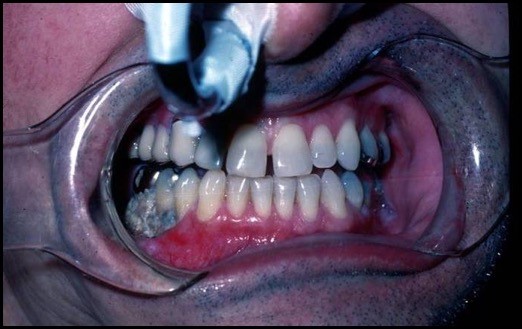

Fig. 1. Mandibular osteoradionecrosis. Marx Stage I with exposed mandible. By Worth E.R., M.D.

Fig. 2. Mandibular osteoradionecrosis. Marx Stage III with orocutaneous fistula.

By Worth E.R., M.D.